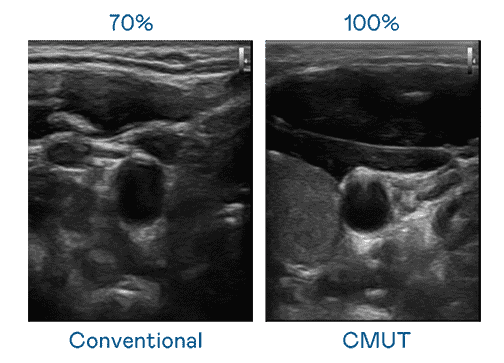

CMUT 技术是一种用电容式微机电元件来产生超音波讯号的技术。。。与传统 PZT 压电式技术相比,,CMUT 频宽增加 30%,,更宽频的超音波讯号让影像解析度大幅提升,,,是实现高影像品质医疗超音波扫描、、、促进精准医疗发展的关键技术。。。

超音波影像的解析度高低,,,首先取决于探头能发出的讯号频宽。。。。z6尊龙 CMUT 可提供高清晰的超音波讯号,,提供高频宽、、高灵敏度、、、、影像纹理细节更高的超音波影像,,协助医护人员缩短影像判读时间及利用精准的医疗影像进行诊断。。。